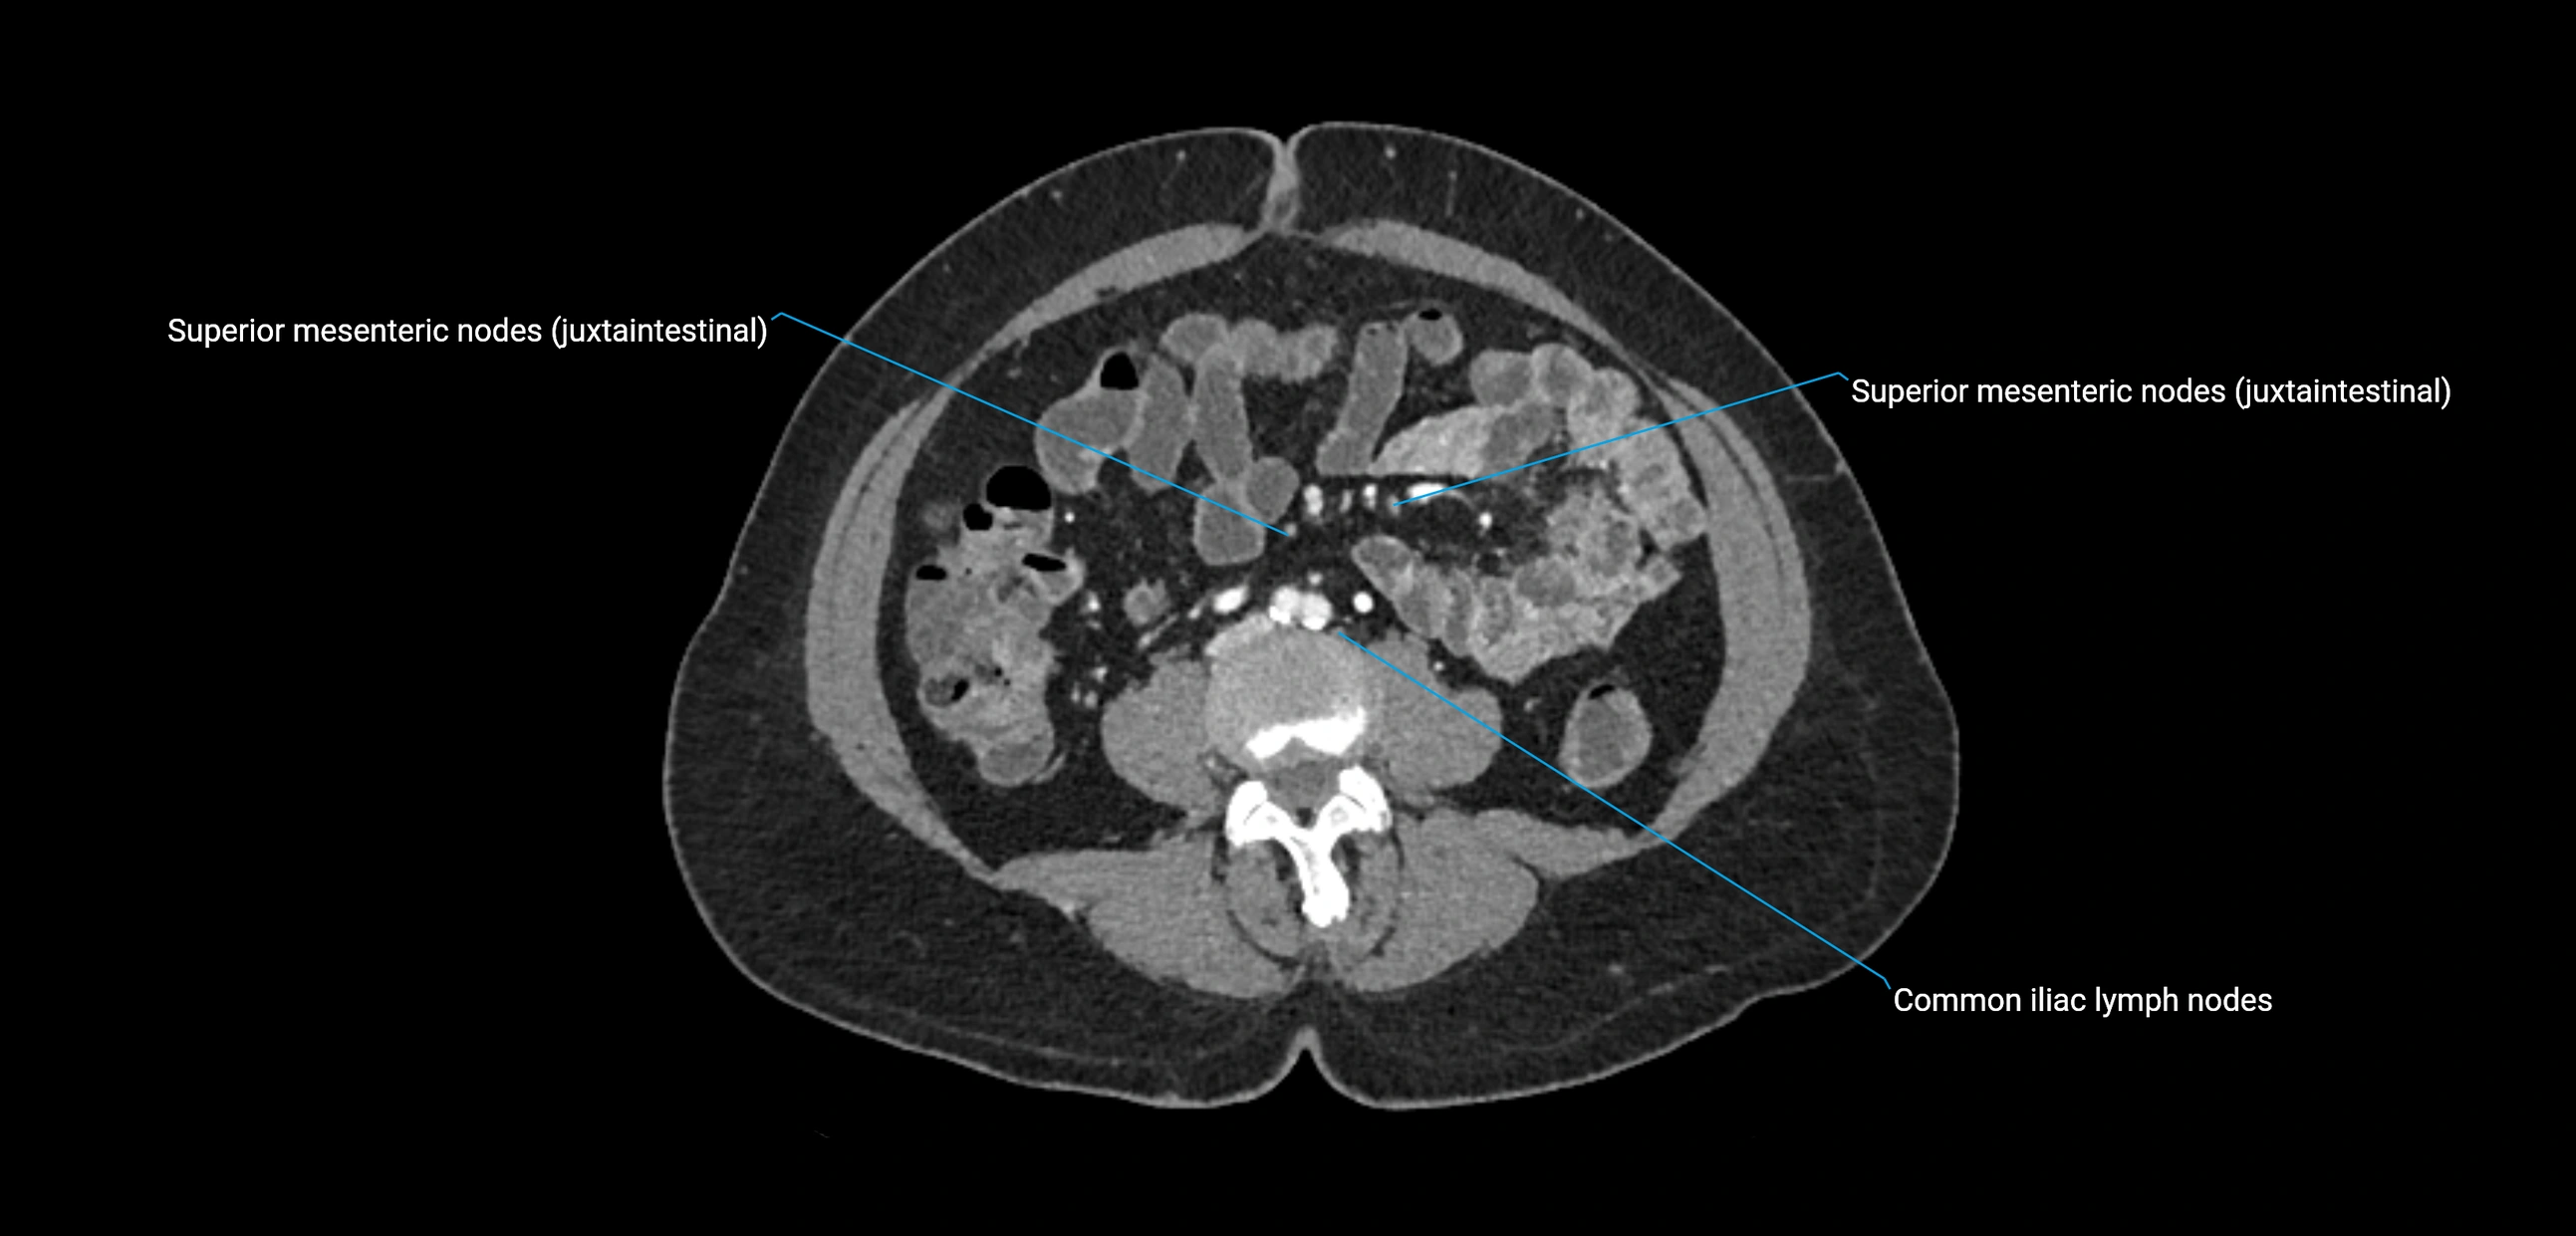

CT Appearance

CT Pre-Contrast:

• Nodes appear as soft-tissue density nodules adjacent to the aorta and IVC

• Calcification may be seen in chronic infections (e.g., tuberculosis)

CT Post-Contrast:

• Normal nodes enhance homogeneously

• Malignant nodes may show heterogeneous enhancement, central necrosis, or conglomerate formation

• Size >1 cm short axis is suspicious, though morphology and distribution are equally important